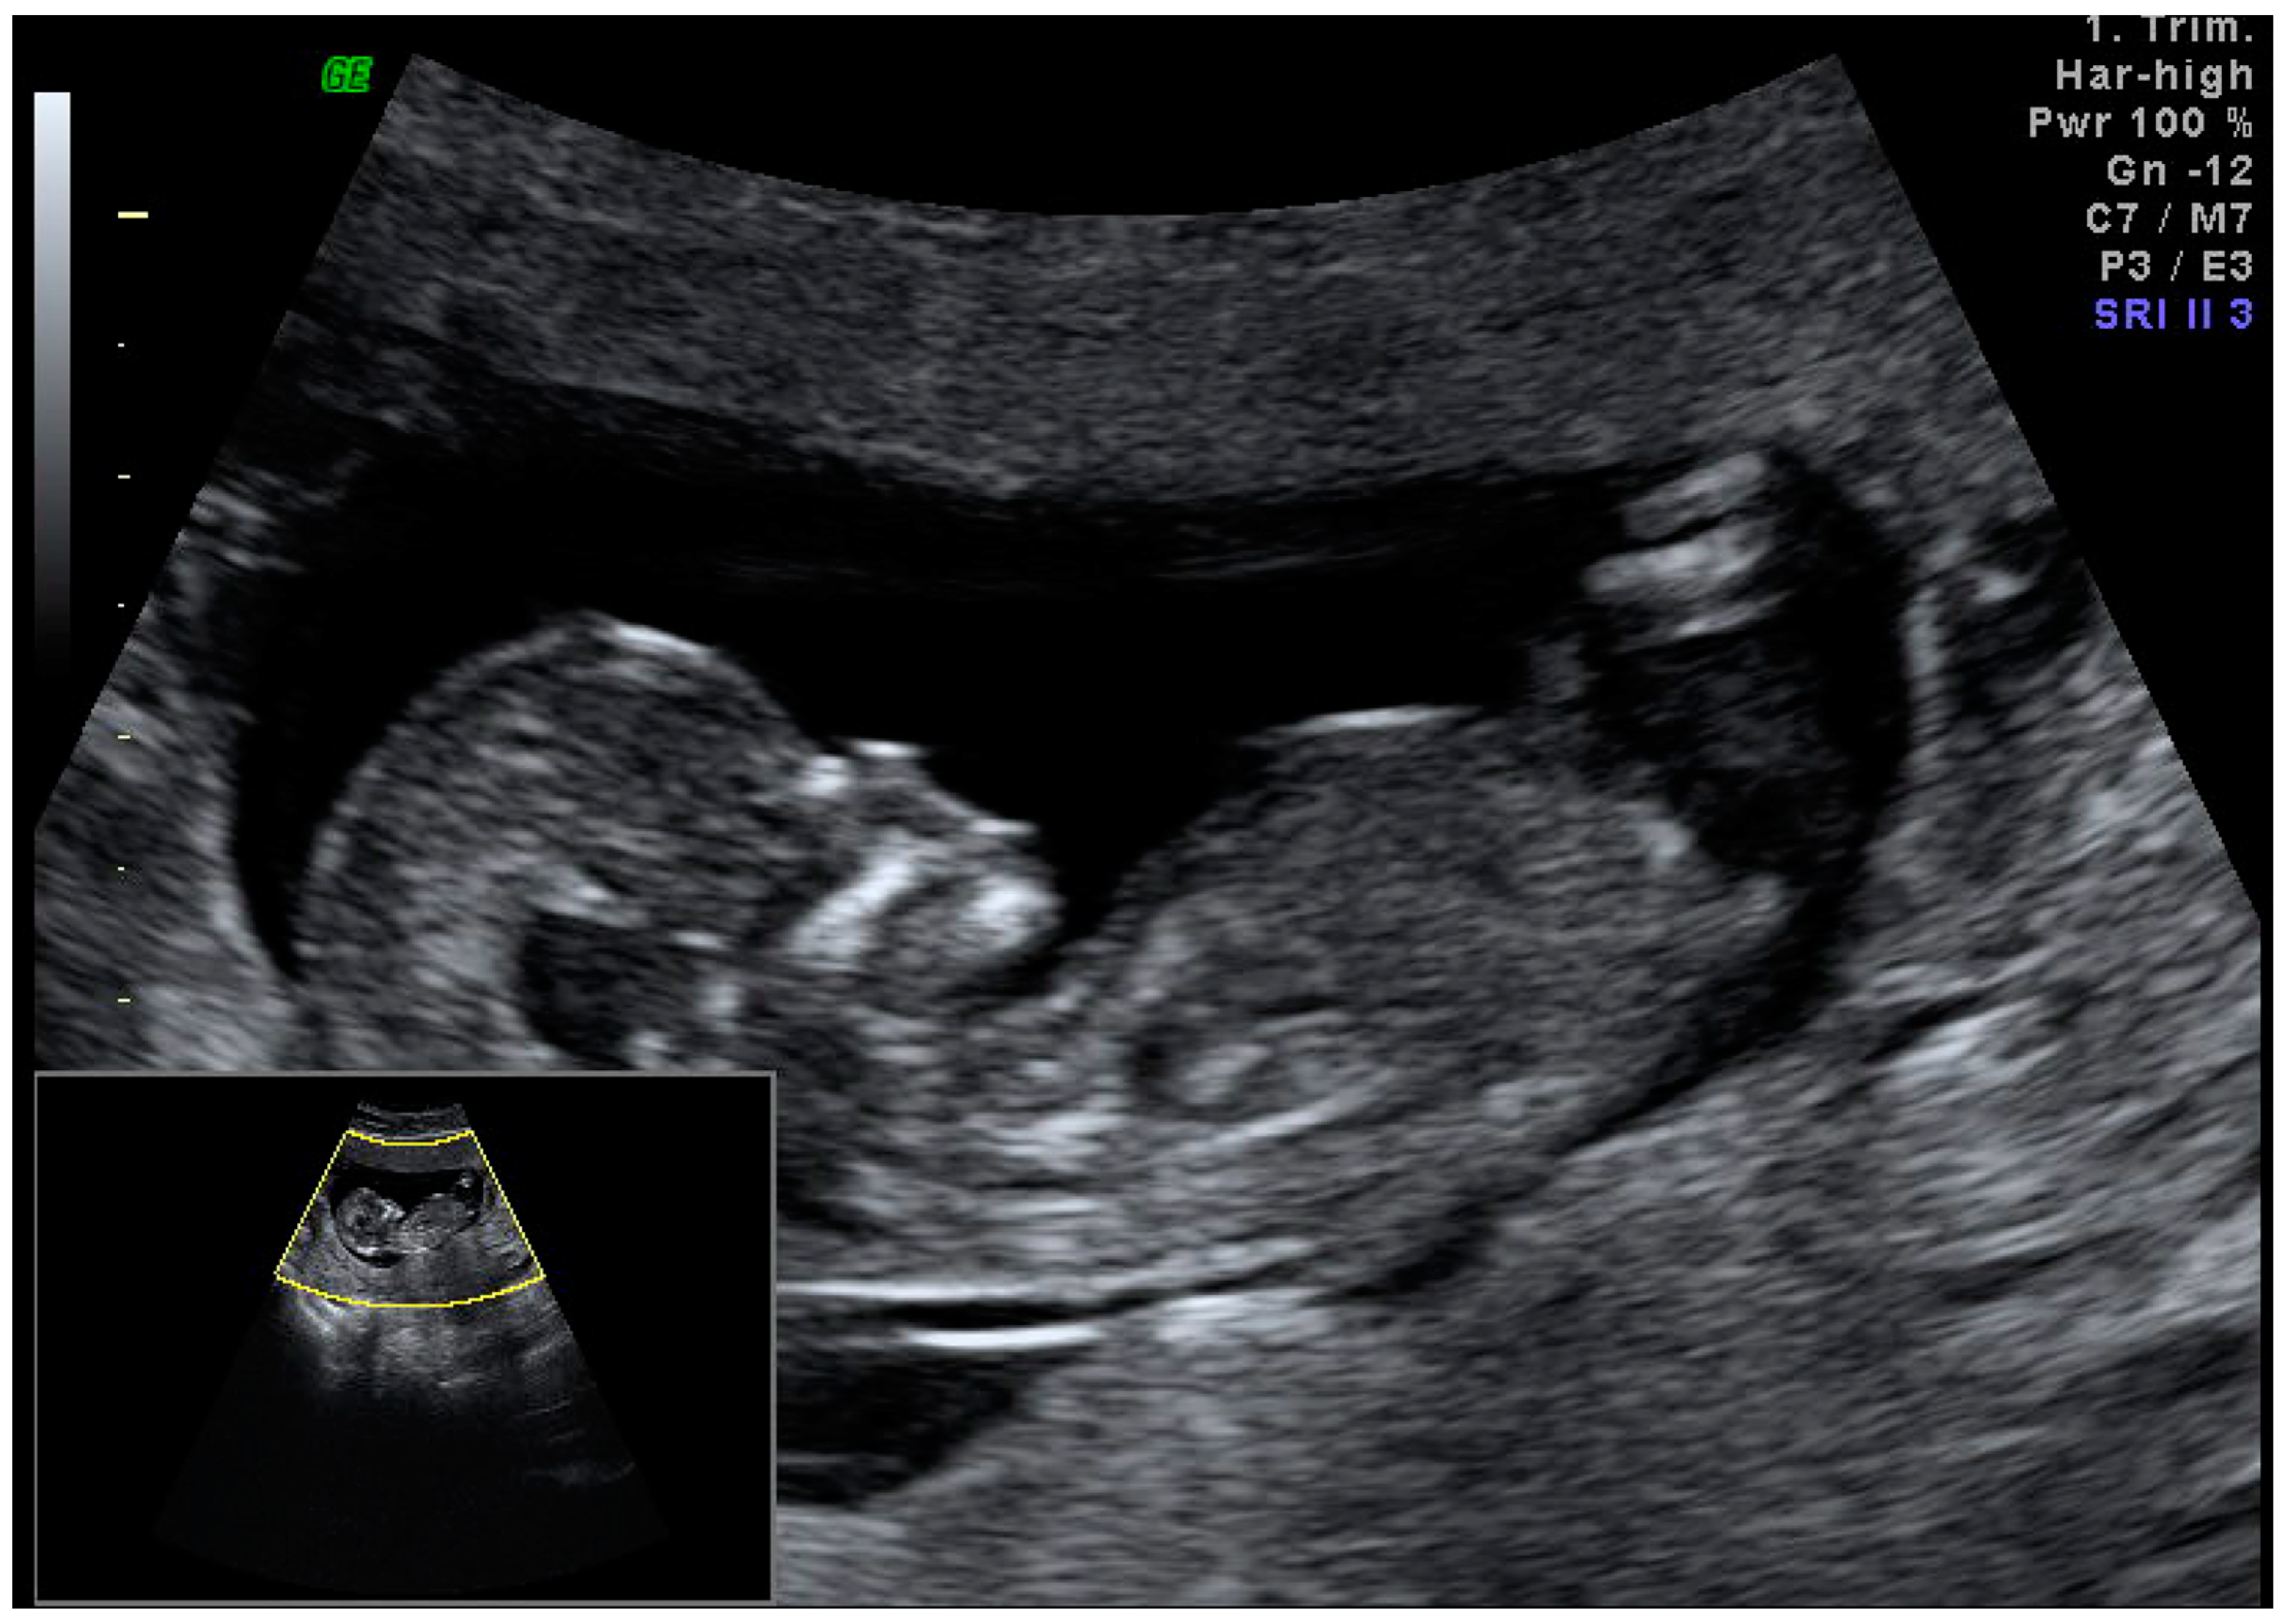

Case Report